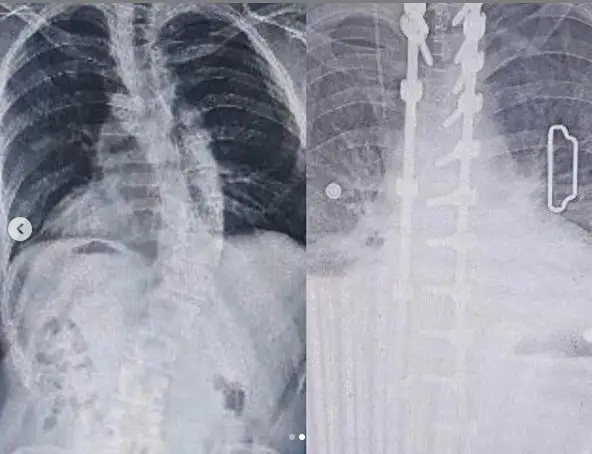

Осы уақытқа дейін сырқаты жайлы ешбір сұхбатында жақ ашпаған Кәрімов бұрын-соңды ешкімге айтпаған, басынан өткен қиын кезеңдерін әлеуметтік желіде парақшасына жазды. Бала кезінде сколиоз ауруына шалдығып, омыртқа жотасының қисаюы салдарынан пайда болған дерттен қатты қиналып келгенін айтады. Жылдар өте ауруы асқынған Кәрімов Кореяда омыртқасына ота жасатуға мәжбүр болыпты. Ол арнайы бейнеролик жүктеп, сырқаты жайлы жазба қалдырды.

«Әлі есімде, мен 15 жасымда сырқаттанып қалдым. Омыртқам қатты мазалай бастады. Мектепте оқып жүрген кезім. Бастапқыда өзімді бірқалыпты сезінетінмін, ешбір жерім ауырмайтын, сырттай да аса қатты білінген емес. Кейіннен арқамның оң жағында дөңес пайда бола бастады. Сөйтсем, ол омыртқаның қатты қисайып кетуінен екен. Уақыт өте жағдайым ушығып, ақыр соңында сол жақ қабырғам көріне бастады. Әрине, жас жігіт болған соң, сырт көзден ұялып, тіпті, өзіме ұнаған киімді кие алмайтынмын. Адамдармен жақын қашықтықта жүруге де қысылатынмын, себебі, алға шығып кетсем бірден байқап, омыртқамдағы олқылық жайлы сұрап қалуы мүмкін еді. Барлық сахналық киімдерімді де ешбір деффект байқалмайтындай етіп қайта тігуге тура келетін. Уақыт өте елден жасырып жүрген дерт асқына бастады. Тез шаршап қаламын. Мәселен, екі сағат ән айту үшін бес сағат бойы қимылдамай жату керек. Өз-өзіме келіп, қайта тұру үшін кейде бес сағаттың өзі аздық ете бастады. Кейіннен маған тек ота жасату керек болды. Басқа таңдау жоқ. Бірақ, ота жасатуға қолымда қажетті қаражат болмады. 9 жыл өткен соң мен Кореяға ұшып келдім. Профессор сырқатымның асқынып кеткенін, маңызды таңдау жасау керектігін айтты. Осылайша өткен жылы мен 11 сағатқа жалғасқан ауыр отаны басымнан өткіздім», – деп жазды Кәрімов.